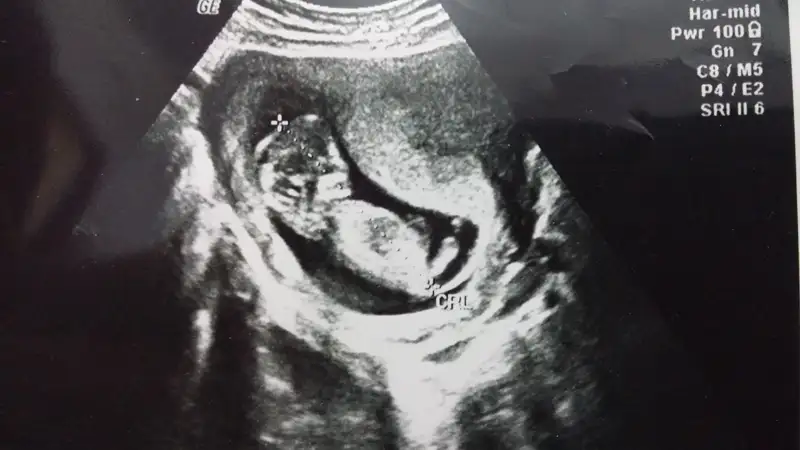

Pipiyok büyük ihtimal kız dedikoydum göremediler pozisyonu uygun değil dediler bi kaç kişi kız dedi

hayırlı olsun cnm şanslı kadınların kızı olur derler bizde rabbim önce hayırlısını ve sağlıklısını versin tabiPipiyok büyük ihtimal kız dedi